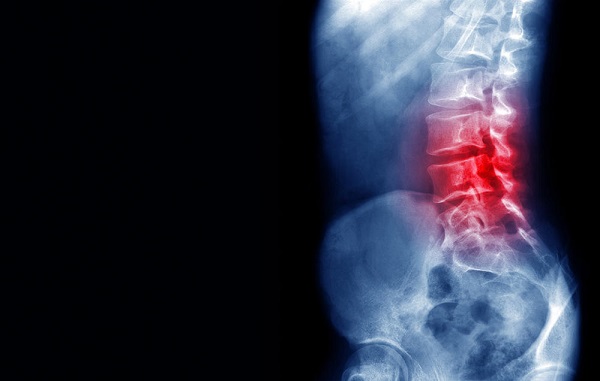

اگر به تازگی تصادفی داشته اید، داروهای خوراکی استروئیدی مصرف می کنید (که می تواند استخوان ها را تضعیف کند)، یا پوکی استخوان در شما تشخیص داده شده است، هر گونه کمر درد باید جدی گرفته شده و به پزشک مراجعه کنید. شما ممکن است شکستگی ستون فقرات داشته باشید که می تواند به کاهش قد، وضع اندامی خمیده و حتی مشکلات تنفسی و گوارشی منجر شود.